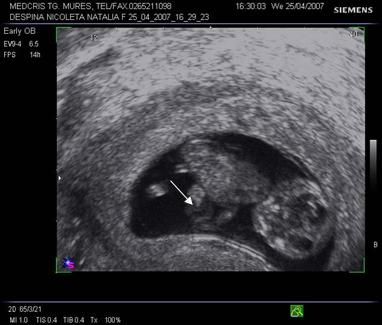

Fig. nr.125 Omfalocel la o sarcina de 12 saptamani ( zona anecogena marcata cu caliper )

Fig. nr.126 Acelasi fat ca in figura precedenta, sectiune transversala abdominala, cu ecou Doppler la periferia omfalocelului